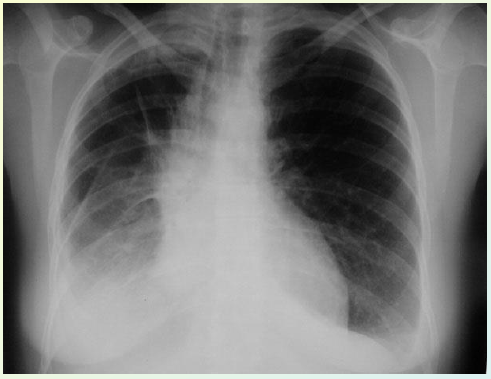

Dit is misschien wel de meest gekende vorm van medische beeldvorming en men benoemt dit vaak als: een foto nemen. Hier kan men ook verscheidene soorten onderscheiden:

• Gewone radiografie: foto van meestal botstructuren

Hoewel dit zeer veel informatie kan opleveren moet men hier voorzichtig mee zijn want de straling die deze foto's maakt (hoge energie) zijn schadelijk voor de mens en kan het DNA aantasten. Deze apparaten moeten dan ook dikwijls gecontroleerd worden door het FANC (=Federaal Agentschap voor Nucleaire Controle).